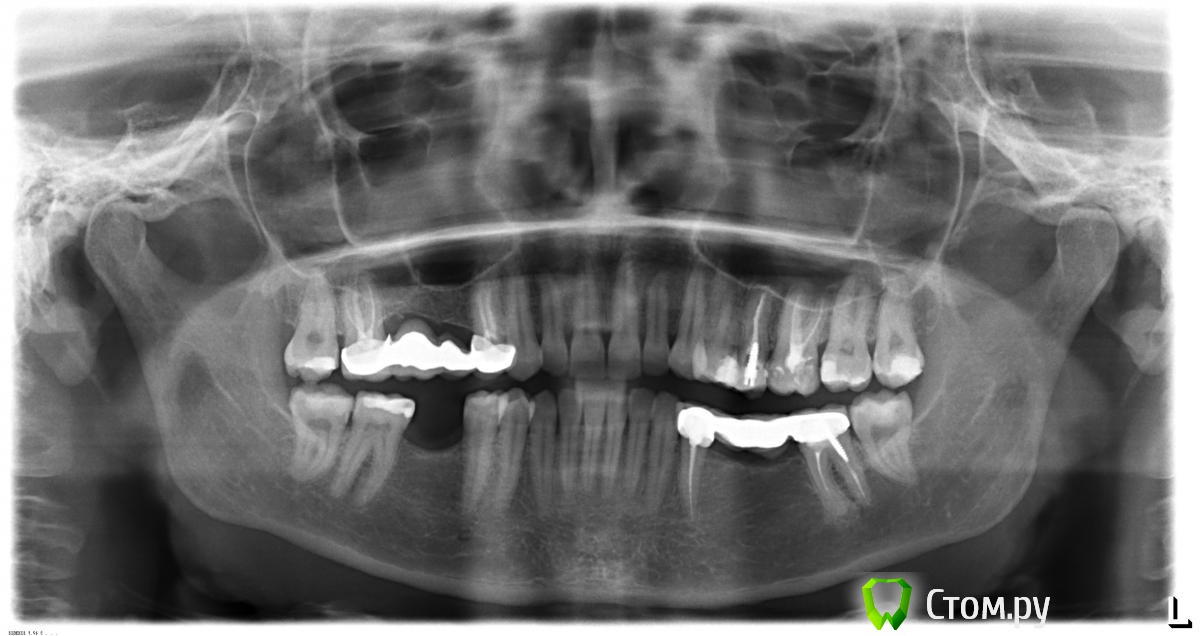

Симба Опубликовано 6 декабря, 2013 Поделиться Опубликовано 6 декабря, 2013 Добрый день. Проблема следующая: Была цель перелечить 25 зуб и поставить на него коронку, а по снимку, доктором предлагается снять мост с нижних зубов (34-37) до постановки верхней коронки, перелечивание и имплантация нижних зубов. Мост стоит 4 года, не беспокоит, по снимку я не ориентируюсь, подскажите, действительно ли это необходимо - снятие моста и лечение нижних? Спасибо. Ссылка на комментарий

DmitrySH Опубликовано 6 декабря, 2013 Поделиться Опубликовано 6 декабря, 2013 На зубе 37 есть хронический очаг воспаления. Ссылка на комментарий